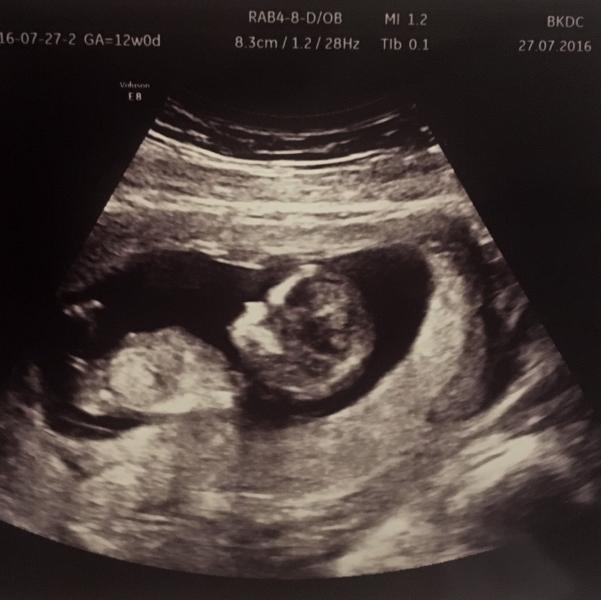

Ну привет! 12недель! Токс пока не отпускает(